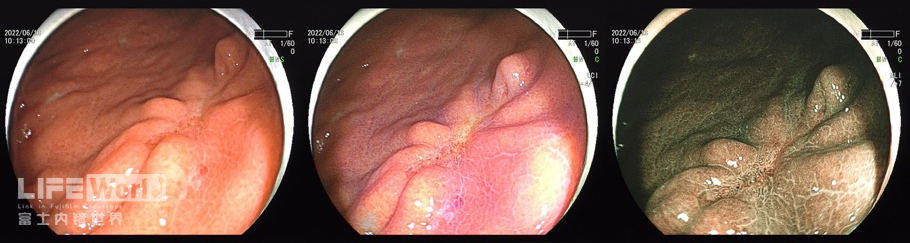

LCI模式:病变为橙黄色,周围黏膜呈紫红色。

白光+LCI+BLI的对比观察。

BLI模式低倍放大观察,可清晰的勾勒出病变的范围,病变的口侧端表面微结构的异型性明显,考虑为癌灶,病变的肛侧端异型性不明显,考虑为上皮内瘤变。